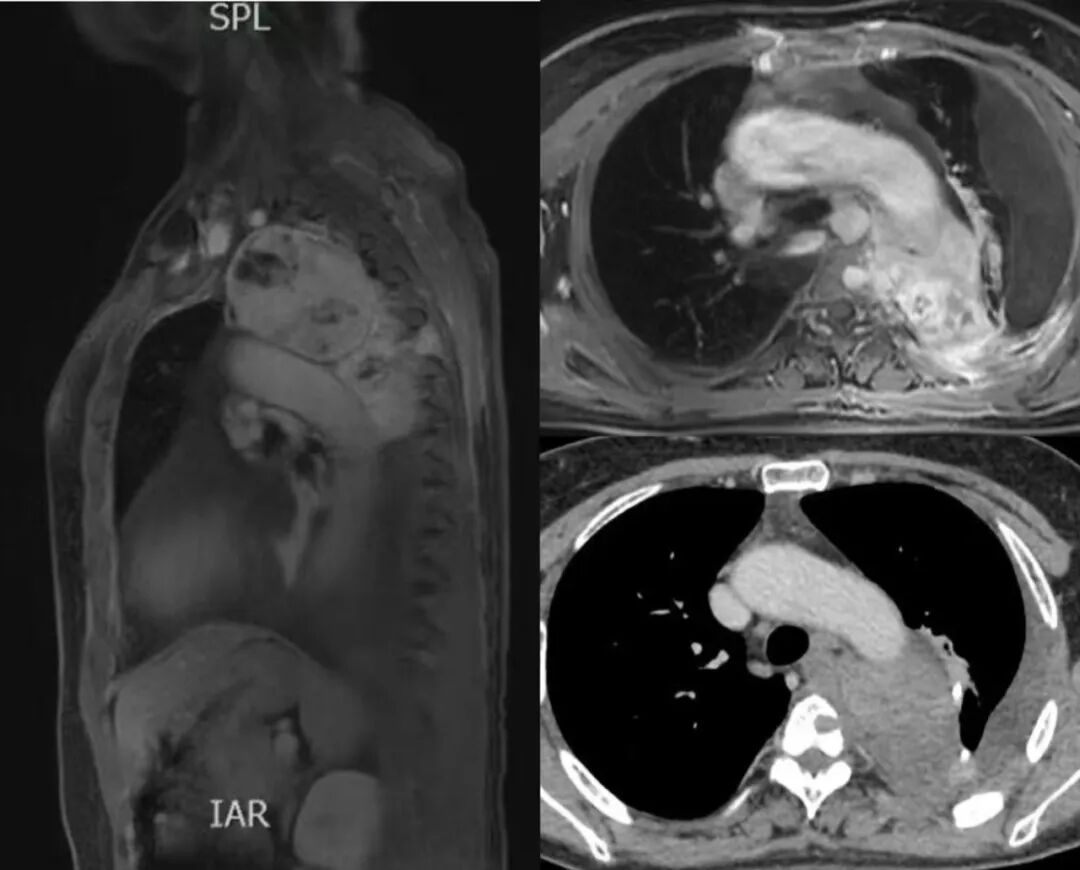

经过全面细致的检查评估,团队发现张女士的病情极其复杂凶险:

1、二次手术粘连难题:首次手术造成的胸腔内广泛粘连,使得手术视野暴露异常困难,如同在“瘢痕迷宫”中操作,大大增加了误伤风险。

2、“雷区”中的肿瘤:

1) 血管“零距离”:肿瘤包绕主动脉弓及部分降主动脉,与血管壁几乎“零距离”,术中剥离极易引发灾难性大出血。

2) 脊柱神经威胁:肿瘤邻近胸椎且造成骨质破坏,操作稍有不慎即可能损伤神经导致术后截瘫。

3) 肺脏受压: 巨大肿瘤已严重压迫左肺。